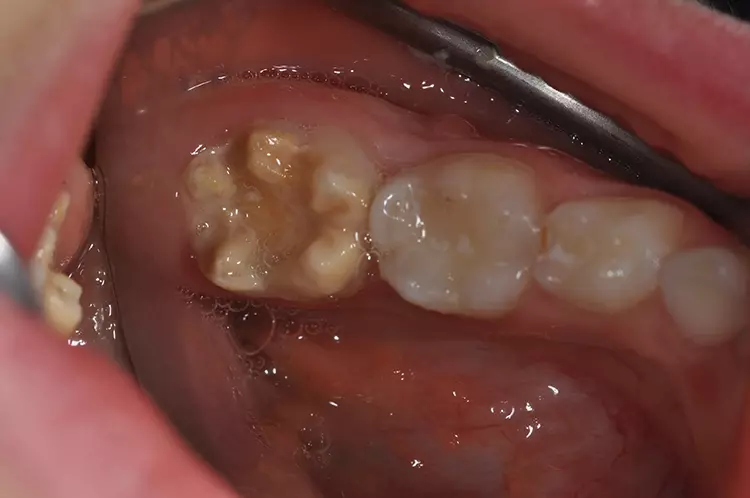

Typisch sind bei der leichten Form der Erkrankung weiße, cremige oder gelblich bis braune Opazitäten (Abb. 1). Im Gegensatz zur Dentalfluorose zeigt sich eine große Variabilität in Form, Farbe und Größe an den Zähnen innerhalb einer Mundhöhle. Bei der schweren Form bricht die Schmelzoberfläche nach dem Durchbruch des Zahnes im okklusalen Kontaktbereich aufgrund der Kaukräfte ein oder die Zähne weisen bereits im Durchbruch Defekte und Hypoplasien auf (Abb. 2).